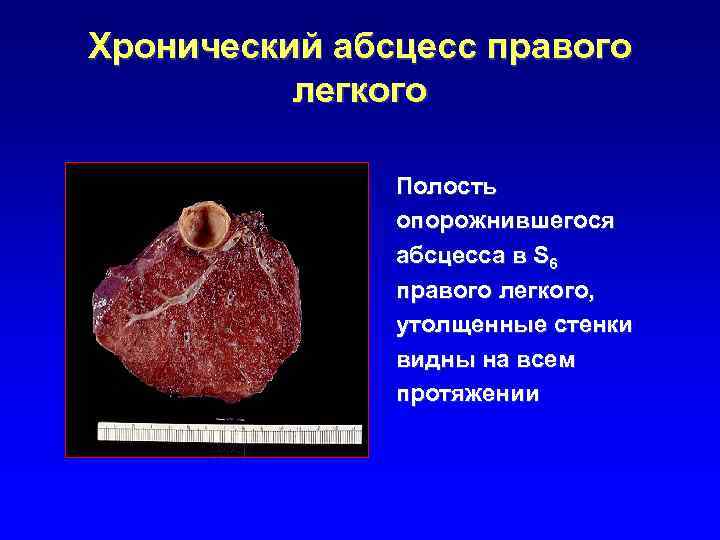

Хронический абсцесс правого легкого Полость опорожнившегося абсцесса в S 6 правого легкого, утолщенные стенки видны на всем протяжении